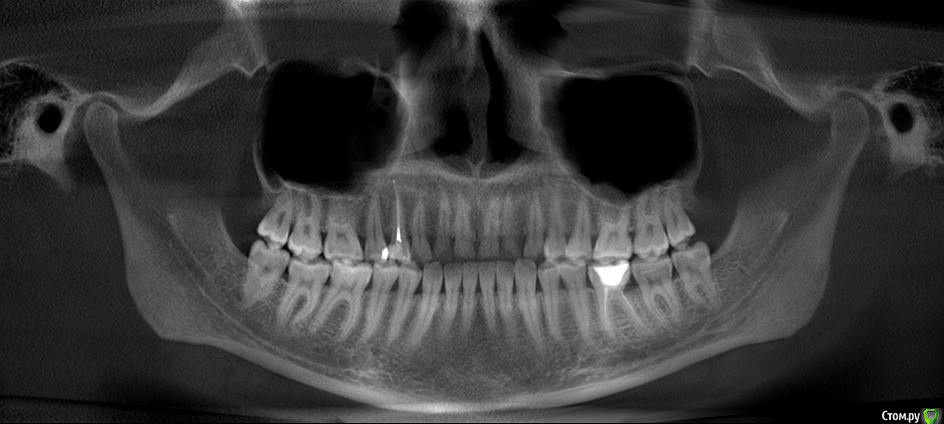

Прикрепляю не очень удачные скриншоты из КТ, которая была сделана через 4 дня после пломбировки каналов. К сожалению, других снимков на руках нет, только КТ.

post-58215-0-93459700-1563461560_thumb.jpg

post-58215-0-74686000-1563461568_thumb.jpg

post-58215-0-40814600-1563461576_thumb.jpg

post-58215-0-92104400-1563461580_thumb.jpg

Поддерживаю. По снимку все выглядит хорошо.